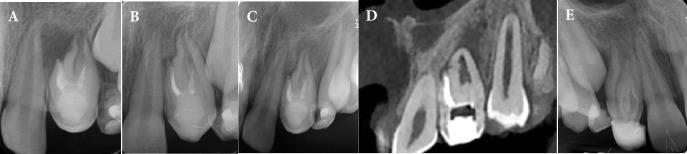

The superior lateral incisors are primarily affected by the developmental deformity known as dens invaginatus (DI). Oehler's type III DI has the highest complexity rendering a root canal treatment (RCT) an arduous challenge for this type, so early diagnosis and treatment before pulp involvement are important. This report presents two maxillary lateral incisors with type IIIb DI, the left one being associated with a periapical lesion and the right one with normal pulp. A nine-year-old boy was referred to our clinic complaining of mobility of the maxillary left lateral incisor (LLI) associated with gumboil throughout the previous two months. Periapical radiolucency was visible on radiographs, as well as an invagination that crosses the apical foramen from the pulp chamber in both maxillary lateral incisors. The pulp of the main canal of LLI was vital and pseudo canals were necrotized and associated with chronic apical abscess. Based on the condition of the main pulp of maxillary lateral incisors, two separate treatments were carried out. RCT was done only for the pseudo canals in the LLI, while the main root canal was preserved. The right maxillary lateral incisor (RLI) had vital pulp with normal periapical tissue So the invagination was sealed as the tooth was erupting. During the one-year follow-up period, the development of the root in LLI with a thick root wall and closed apex was observed in the periapical radiograph but pseudo canals became infected and the tooth became symptomatic, therefore retreatment for pseudo canals was carried out. The RLI root was developed and the tooth was clinically asymptomatic, so it didn't need further treatment. Maintaining pulp vitality is crucial for type III Dens invaginated young permanent teeth since it could support root formation and improve long-term prognosis, and in cases with pulp involvement, non-surgical RCT is clinically predictable.

上颌侧切牙主要受一种称为牙内陷(DI)的发育畸形影响。奥勒(Oehler)III型DI最为复杂,给这种类型的牙齿进行根管治疗(RCT)是一项艰巨挑战,因此在牙髓受累之前进行早期诊断和治疗很重要。本报告展示了两颗IIIb型DI的上颌侧切牙,左侧的伴有根尖病变,右侧的牙髓正常。一名9岁男孩因上颌左侧侧切牙(LLI)在过去两个月里出现松动并伴有牙龈脓肿而被转诊至我们诊所。根尖片可见根尖周透射影,两颗上颌侧切牙均有从牙髓腔穿过根尖孔的内陷。LLI主根管的牙髓活力正常,而假根管坏死并伴有慢性根尖脓肿。根据上颌侧切牙主牙髓的情况,进行了两种不同的治疗。仅对LLI的假根管进行了RCT,而主根管得以保留。右上颌侧切牙(RLI)牙髓活力正常,根尖周组织正常,因此在牙齿萌出时封闭了内陷。在一年的随访期内,根尖片观察到LLI牙根壁增厚且根尖闭合,但假根管感染,牙齿出现症状,因此对假根管进行了再治疗。RLI牙根发育正常,临床无症状,因此无需进一步治疗。对于III型牙内陷的年轻恒牙,保持牙髓活力至关重要,因为这有助于牙根形成并改善长期预后,而对于牙髓受累的情况,非手术RCT在临床上是可预测的。